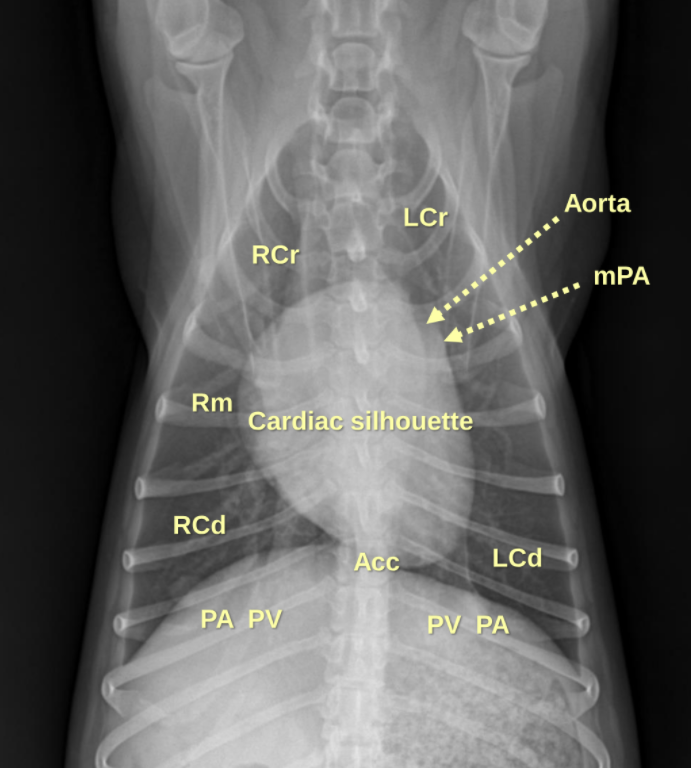

1. Normal Anatomy

| Thorax | |